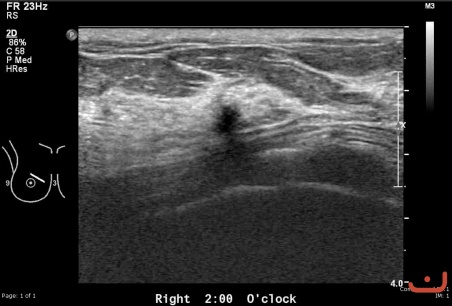

Benign solid mass

Thursday, 30 April 2015

90.83 KB (452 x 306 px)